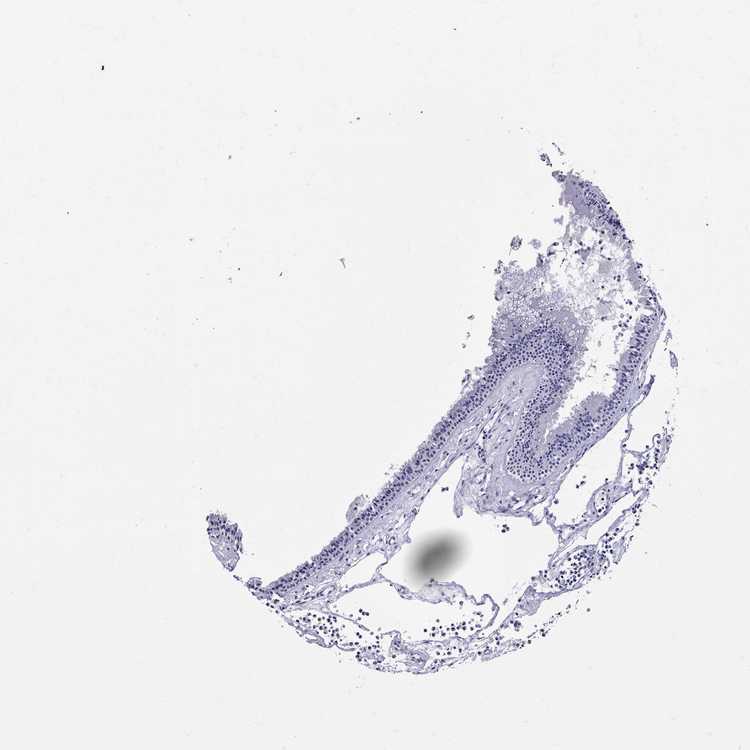

TISSUE PRIMARY DATA NASOPHARYNX Show tissue menu

NASOPHARYNX - Antibody stainingi

Antibody staining in the annotated cell types in the current human tissue is reported as not detected, low, medium, or high, based on conventional immunohistochemistry profiling in selected tissues. This score is based on the combination of the staining intensity and fraction of stained cells.

Each image is clickable and will lead to virtual microscopy that enables deeper exploration of all samples and also displays staining intensity scores, fraction scores and subcellular localization as well as patient and tissue information for each sample.

Antibody HPA071892Antibody CAB025318

Respiratory epithelial cells Not detectedNot detected